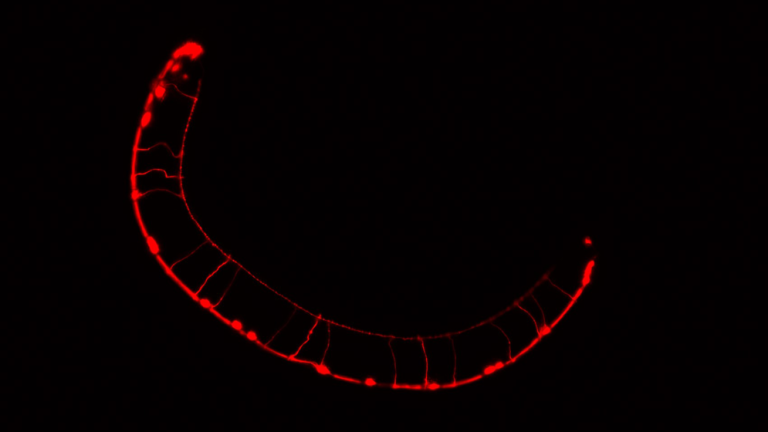

Para la realización del estudio se utilizó como modelo experimental al Caenorhabditis elegans, un gusano microscópico ampliamente empleado en biología por su similitud con muchos procesos moleculares que también ocurren en los animales vertebrados. En su estudio, los investigadores compararon animales con mutaciones en el gen DAF-18 (homólogo del PTEN en humanos) con otros sin estas alteraciones. Los resultados mostraron que las mutaciones en este gen alteran significativamente la transmisión de neuronas inhibitorias denominadas GABAérgicas, cuya función es esencial para mantener el equilibrio entre la excitación y la inhibición en el cerebro.

Sin embargo, al exponer a los gusanos mutantes a β-hidroxibutirato, una molécula que se produce durante el estado metabólico de cetosis inducido por dietas cetogénicas, se logró aminorar los defectos estructurales y funcionales de las neuronas inhibidoras o GABAérgicas. Dichas neuronas son clave para regular el equilibrio de la actividad cerebral y se ha establecido que las fallas en su funcionamiento generan alteraciones comunes en diversos trastornos del sistema nervioso, como los TEA.

Aunque se sabe que las alteraciones en la función de las neuronas GABAérgicas son comunes en pacientes con TEA, así como que las mutaciones en el gen PTEN están fuertemente asociadas con la ocurrencia de estos mismos trastornos, hasta ahora no se había establecido la existencia de un vínculo diferencial entre las deficiencias en el gen PTEN y las señalizaciones inhibidoras y excitadoras en el sistema nervioso. En este sentido, el estudio publicado en eLife logró determinar que, en gusanos C. elegans, las mutaciones en el gen homólogo de PTEN afectan el neurodesarrollo y la función de las neuronas inhibitorias GABAérgicas, pero no así la de las neuronas excitadoras.

Si bien, ya se ha demostrado que las dietas cetogénicas (también conocidas como dietas keto) son eficaces para tratar y aminorar algunos síntomas de los trastornos vinculados con los desequilibrios entre excitación e inhibición en el cerebro, hasta el momento no se sabe mucho sobre los mecanismos subyacentes a tal efecto terapéutico. El descubrimiento del rol de β-hidroxibutirato en la disminución de los defectos del desarrollo neuronal, en gusanos C. elegans con deficiencia en el gen DAF-18, representa un avance en ese sentido.